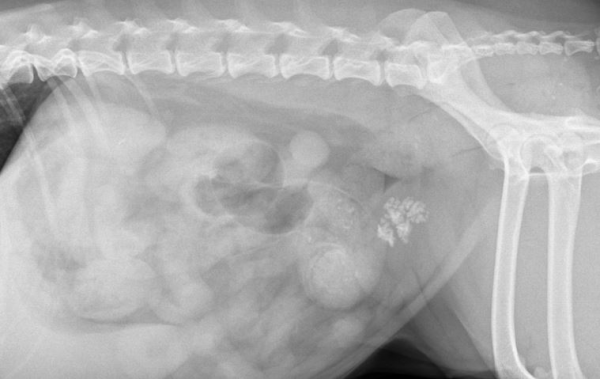

└까미(까명) 방광결석 방사선

특히 복부 초음파는 방광결석의 위치·움직임·크기·요도 폐색 여부를

까미는 방광, 요도, 신장에 결석이 있는 상태로 진단되었습니다.

다행히도 요도 결석이 요도 완전폐색을 유발하지 않은 상태라

응급 수술을 요하지는 않았습니다.